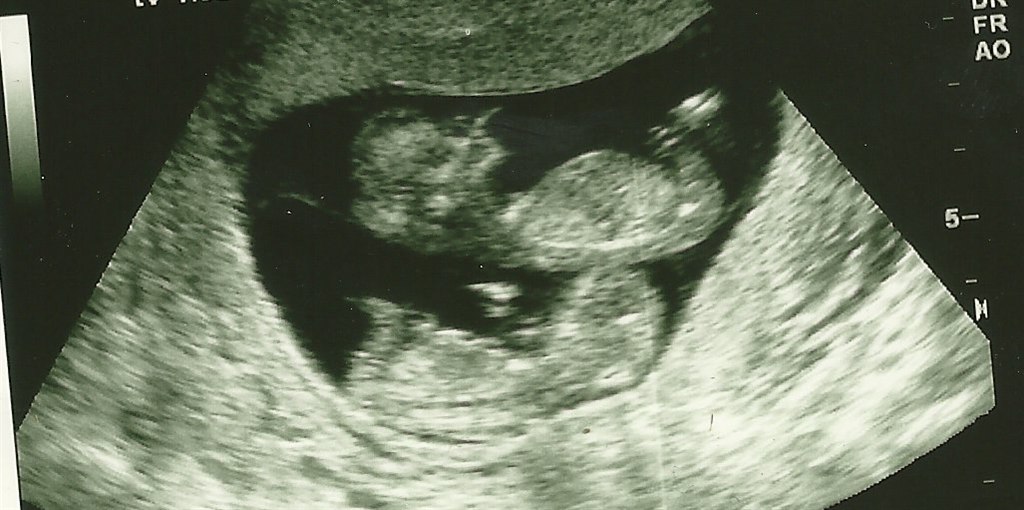

Baby-støv skriver: Jeg var til NF scanning idag. sindsyg nervøs over om bebs var okay.... Om der så ikk lå TO bebser og boksede, de var helt vildt aktive..... Risikotallet 1:7986 og hun fornemmede, den ene var dreng og hun kunne se de var enægget. Så nok begge drenge, men intet er helt sikkert.... Fordi de er enægget, skal jeg til 13 scanninger... og tidlig misdannelse om 14 dage.... Var slet ikk forbedret på dette, da jeg ingen mave har fået endnu eller nogen i familien har tvillinger (hverken min eller kæresten) billeder kommer senere

så kom der billede.... den øverste ville meget gerne møve sig frem og vise sig hele tiden..... rigtig fotogen....

2stks